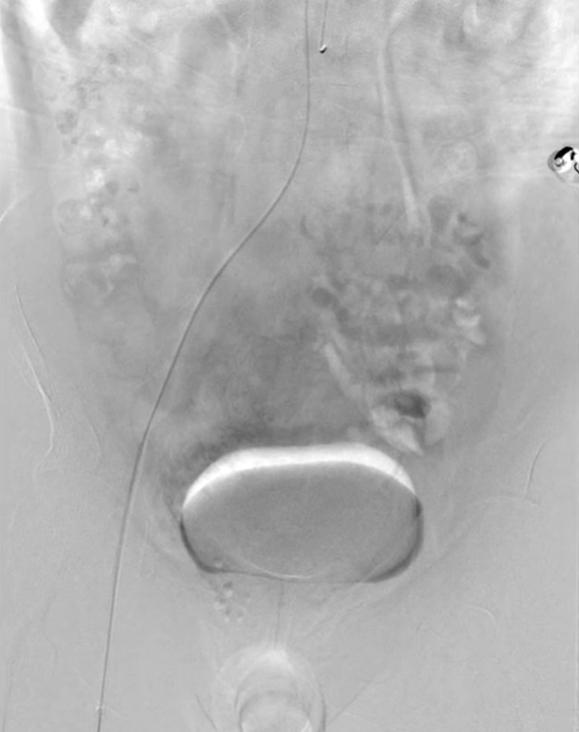

Pelvic MRI (plain scan + contrast-enhanced), as shown in the image above, reveals the following findings: In the mesorectal fat surrounding the middle and lower rectum (marked in red) (Note: Subsequent color processing was applied to the image, with mesorectal fat marked in yellow, same below), numerous "tadpole-shaped" ("bean sprout-like") cord-like, tortuous, and dilated vascular images are visible. Sagittal MRI similarly confirms these findings, demonstrating extensively dilated vascular structures within the mesorectum.

Angiography (gold standard for dynamic diagnosis): Suitable for patients with significant bleeding (daily blood loss >50ml) or those with concomitant vascular malformations. It allows dynamic observation of vascular blood flow direction, helps determine the presence of abnormal shunting, and provides evidence for surgical planning